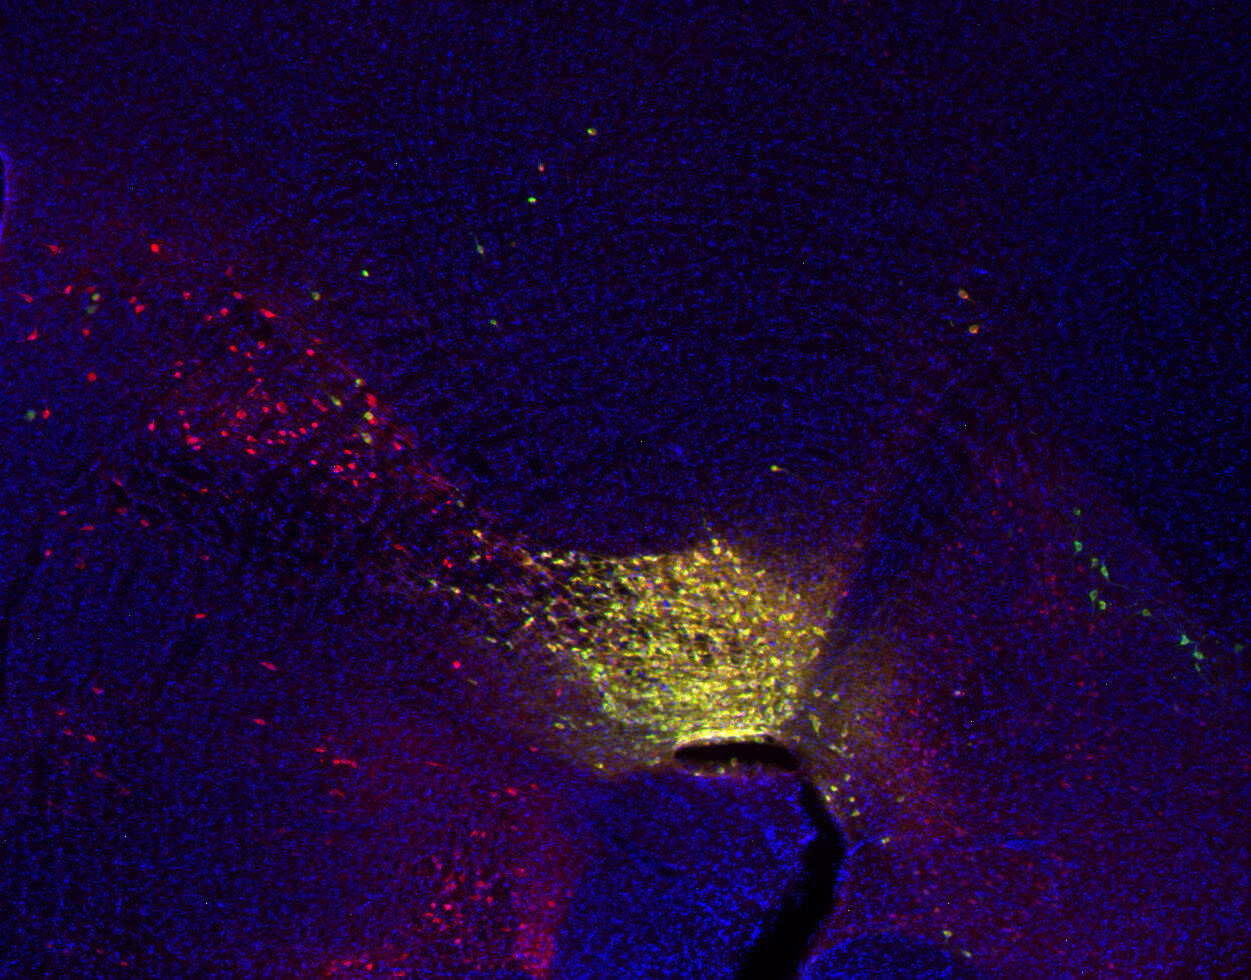

IHC: 1 : 500 up to 1 : 5000 gallery

Immunohistochemistry (IHC) on 4% PFA perfusion fixed tissue with 24h PFA post fixation. Immunoreactivity is usually revealed by fluorescence or a chromogenic substrate. Some antibodies require special fixation methods or antigen retrieval steps. For details, please refer to the ”Remarks” section.